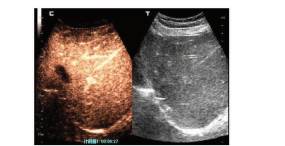

嗜酸性粒细胞增多性重症肝炎1例报告

苏洁, 王景宇, 黄兴, 潘煜, 齐月, 华瑞

2022, 38(1): 164-166. DOI: 10.3969/j.issn.1001-5256.2022.01.026

摘要(1585) HTML (308) PDF (2349KB)(97)

摘要: